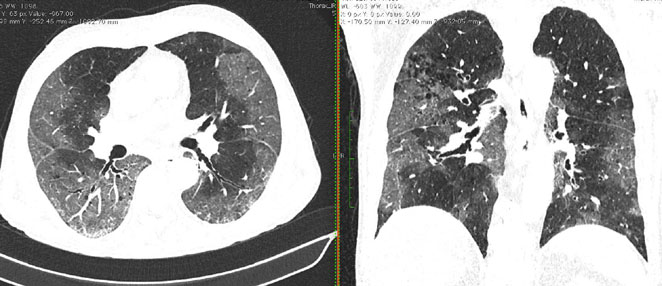

Методы лучевой диагностики применяют для выявления COVID-19 пневмоний, их осложнений, дифференциальной диагностики с другими заболеваниями легких, а также для определения степени выраженности и динамики изменений, оценки эффективности проводимой терапии.

КТ имеет высокую чувствительность в выявлении изменений в легких, характерных для COVID-19. Применение КТ целесообразно для первичной оценки состояния ОГК у пациентов с тяжелыми прогрессирующими формами заболевания, а также для дифференциальной диагностики выявленных изменений и оценки динамики процесса. КТ позволяет выявить характерные изменения в легких у пациентов с COVID-19 еще до появления положительных лабораторных тестов на инфекцию с помощью МАНК. В то же время, КТ выявляет изменения легких у значительного числа пациентов с бессимптомной и легкой формами заболевания, которым не требуется госпитализация. Результаты КТ в этих случаях не влияют на тактику лечения и прогноз заболевания при наличии лабораторного подтверждения COVID-19. Поэтому массовое применение КТ для скрининга асимптомных и легких форм болезни не рекомендуется.

15. Рекомендации по формированию описаний и оценке изменений в легких и ОГК при имеющейся/подозреваемой пневмонии COVID-19 представлены в Приложении 1.